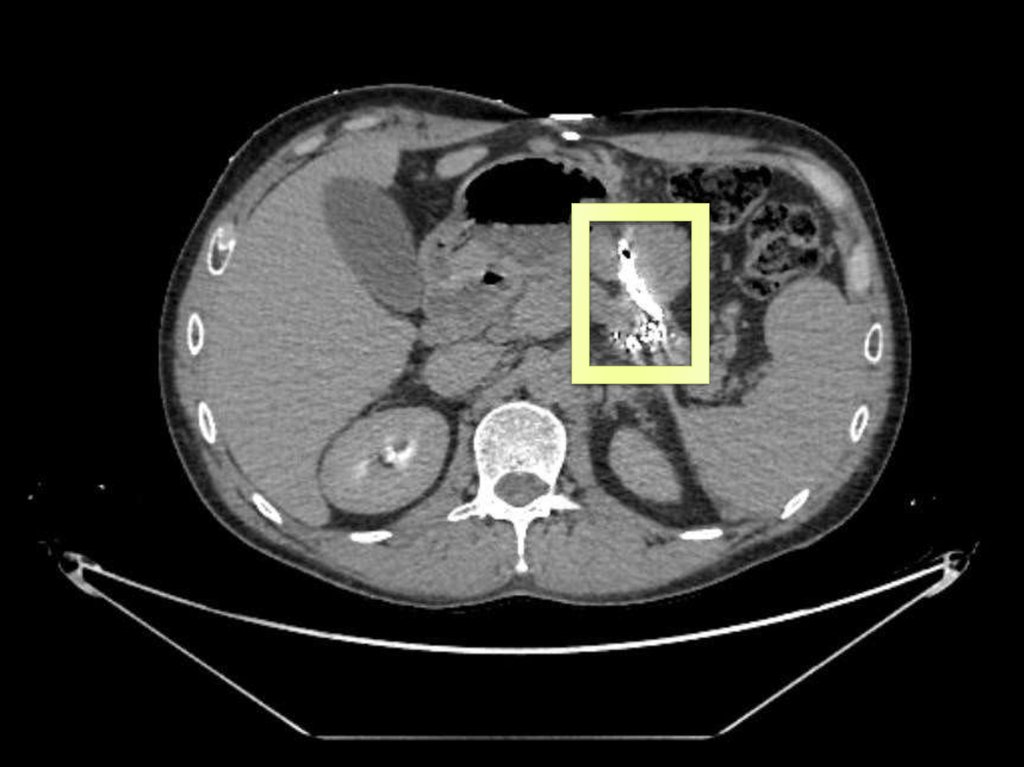

15. По калибру селезеночная вена превышает артерию в 1.5-2 раза